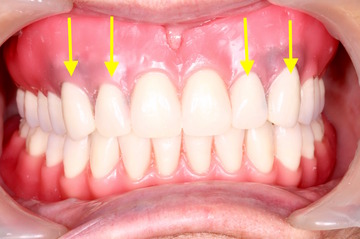

上が総入れ歯、下がレジリエンツテレスコープ義歯です。